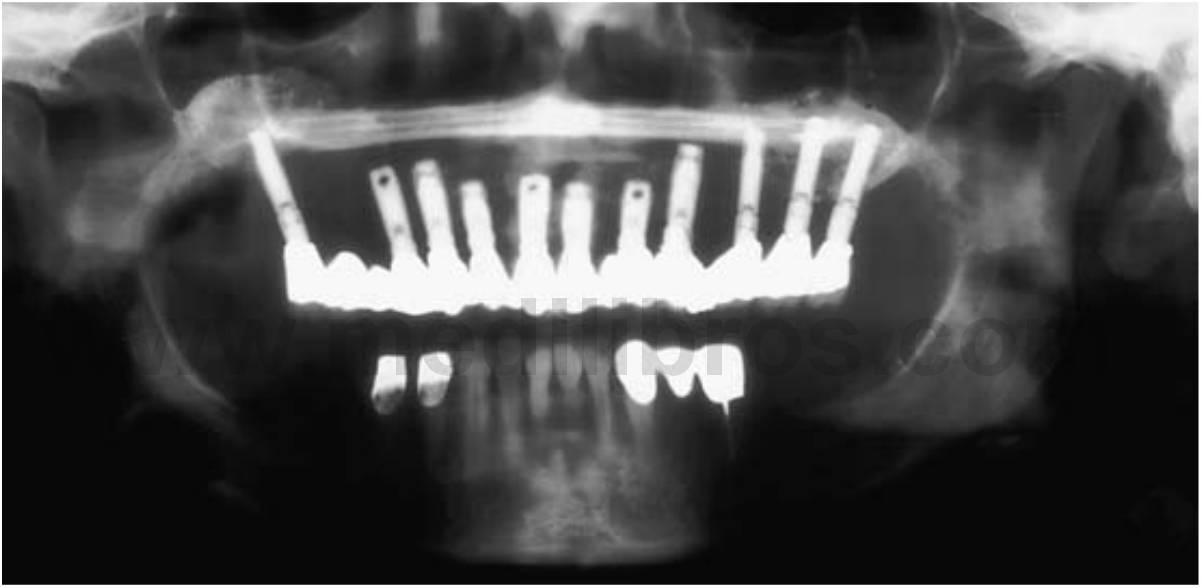

Una razón primaria para considerar los implantes dentales para sustituir los dientes perdidos es el mantenimiento del hueso alveolar (fig. 1-26). El implante dental colocado dentro del hueso sirve a la vez de anclaje para el aparato prostético y como uno de los mejores procedimientos de mantenimiento preventivo en odontología. Se puede aplicar tensión y presión al hueso circundante al implante. como resultado, se invierte la disminución en la trabeculación del hueso que aparece después de una extracción dentaria. Hay un aumento de las trabéculas óseas y en la densidad cuando se inserta el implante y empieza a funcionar. El volumen óseo total también se mantiene con un implante dental.

Incluso los injertos óseos de cresta ilíaca en las mandíbulas, que suelen ser reabsorbidos durante los 5 siguientes años cuando no hay inserción de implante, son estimulados y mantienen el volumen óseo total y la integración del implante. Un implante endoóseo puede mantener el ancho y alto del hueso mientras que el implante se mantenga en buena salud. Al igual que para un diente, la pérdida de hueso periimplantario puede medirse en décimas de milímetro y puede representar más de la veinteava parte de la estructura pérdida, en comparación con la reabsorción que se produce con las prótesis removibles.

El beneficio del mantenimiento del hueso compensa especialmente en la arcada edéntulo maxilar. La arcada maxilar también debería ser tenido en cuenta, en vez de emplear los implantes solo en la arcada mandibular edéntula, aunque los principales problemas mecánicos con las dentaduras aparezcan en esta arcada. Una vez que las prótesis con implante están colocadas para soportar y retener la restauración mandibular, se sigue perdiendo hueso en la región maxilar y el paciente puede eventualmente quejarse de pérdida de retención e incapacidad para funcionar de la dentadura maxilar.

La pérdida de estética facial suele notarse primero en la arca da maxilar, con la pérdida del borde bermellón del labio, el aumento de longitud del labio maxilar y la falta de soporte óseo facial. Los implantes deberían emplearse para la pérdida ósea continuada y prevenir las complicaciones posteriores observadas en la arcada maxilar (figs. 1-27 a 1-31).